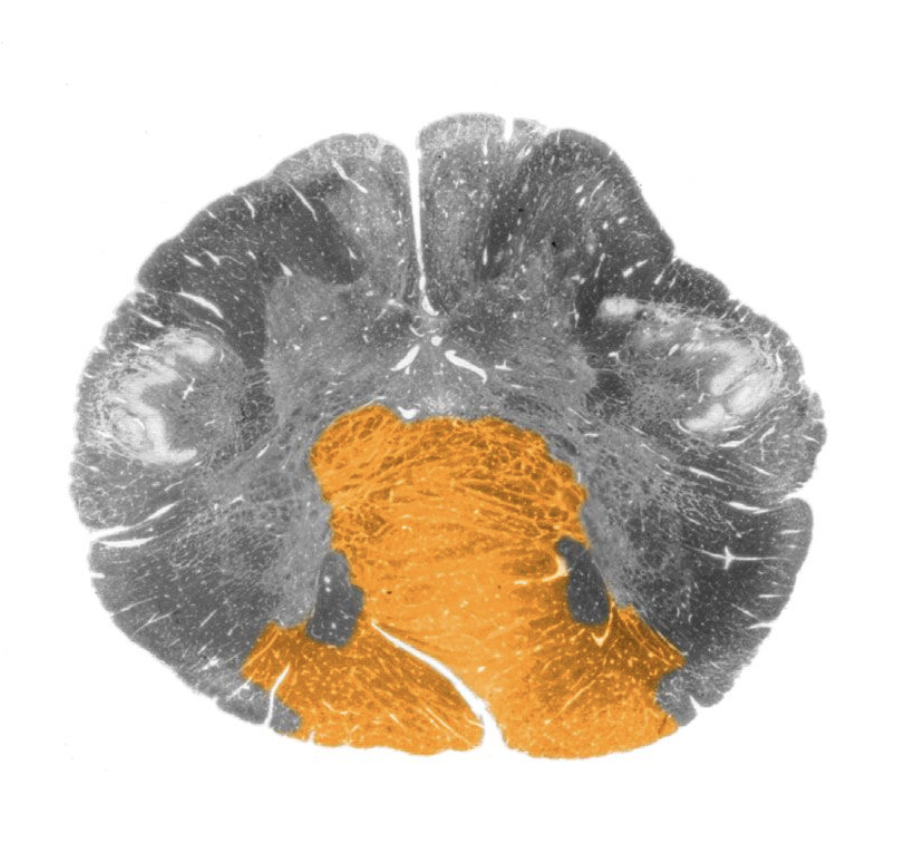

Dorsal columns

White matter region between the dorsal horns of the spinal cord containing the gracile and cuneate tracts.

Dorsal spinocerebellar tract

Ascending sensory tract of the spinal cord originating in the dorsal nucleus of Clarke and terminating in the cerebellum (via the inferior cerebellar peduncle); this tract conveys proprioceptive information from the lower body.

Gracile tract

Medial portion of the dorsal columns comprising the central processes of dorsal root ganglion axons that convey mechanosensory information from the lower body. Also referred to as the "fasciculus gracilis."

Dorsal column nuclei

Gracile nucleus and cuneate nucleus; contain the second-order sensory neurons that relay mechanosensory information from peripheral receptors in the body (excluding the face) to the thalamus via the medial lemniscus. The dorsal column nuclei are located in the lower medulla.